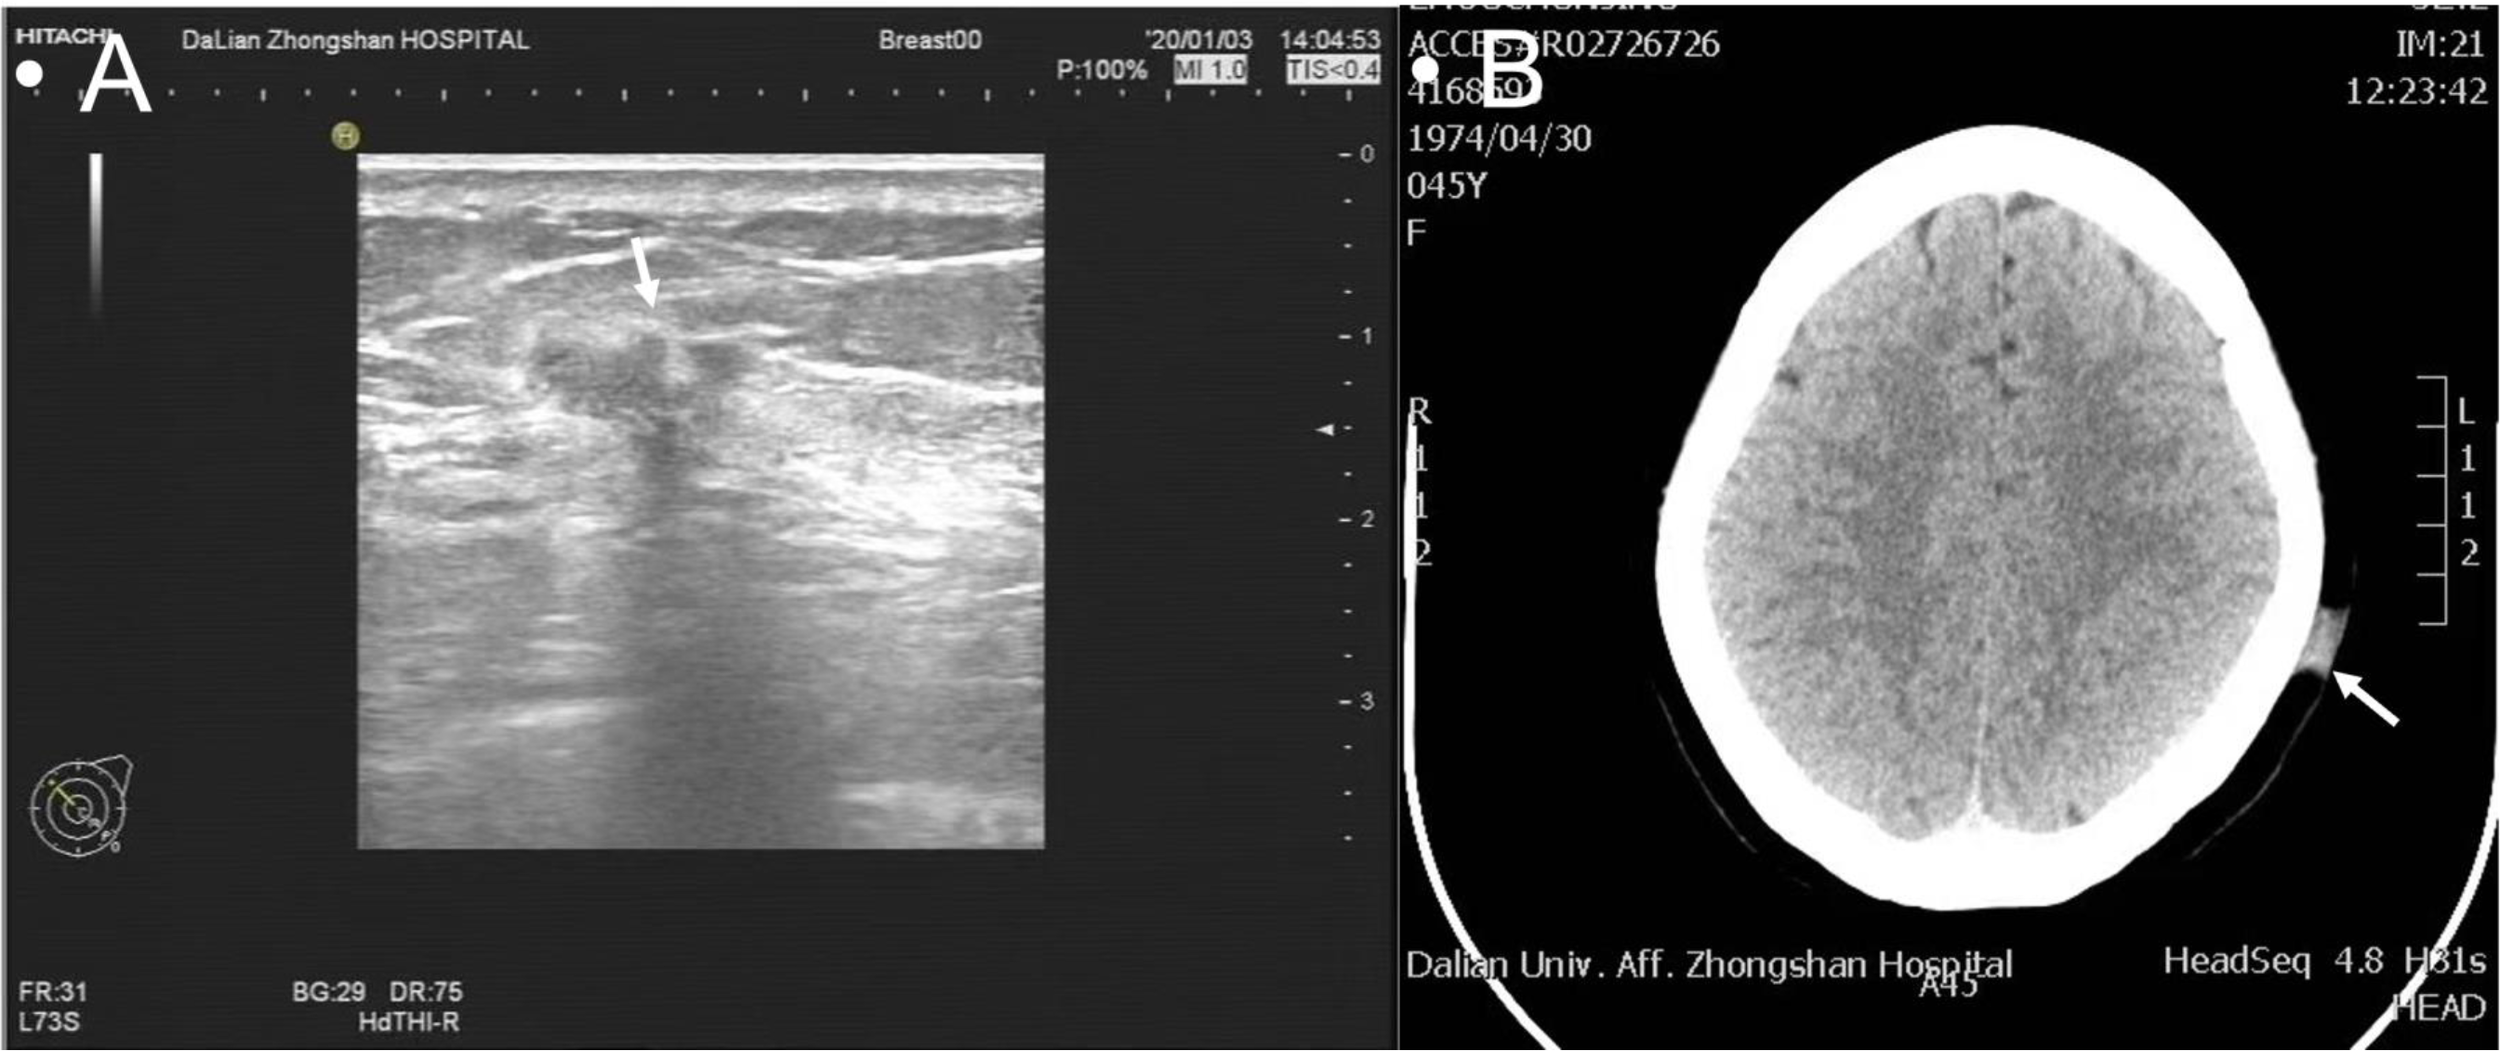

Upon the recent scalp presentation, the physical exam showed a 2.5 × 2.0 × 0.5-cm flat hard, well-demarcated erythematous lesion without ulcerations (Figure 1A). Left breast ultrasound revealed multiple nodular masses with calcifications [breast imaging report and data system (BI-RADS) category 6], and head computed tomography (CT) showed a 1.3-cm hyperdense patchy lesion (Figures 2A, B). Dermatology was consulted, and a biopsy was obtained. The final pathology reported skin metastatic breast cancer with Ki-67 of 20%, positive ER, PR, and negative ErbB2 (Supplementary Figures 1A–D). The patient was eventually diagnosed with Stage IV (rpT1cN1M1) recurrent IDC.

Figure 2

Multiple nodular masses with calcifications on ultrasound classified as BI-RADS 6 (A); a 1.3-cm hyperdense patchy lesion on CT scan (B).